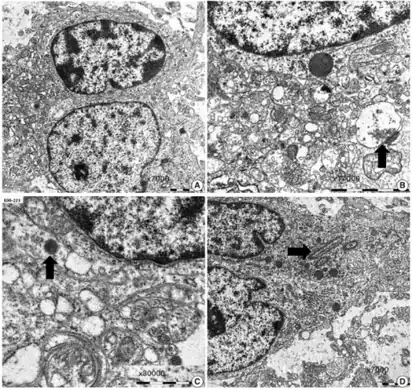

a-d)Ultrastructural findings of dysembryoplastic neuroepithelial tumors